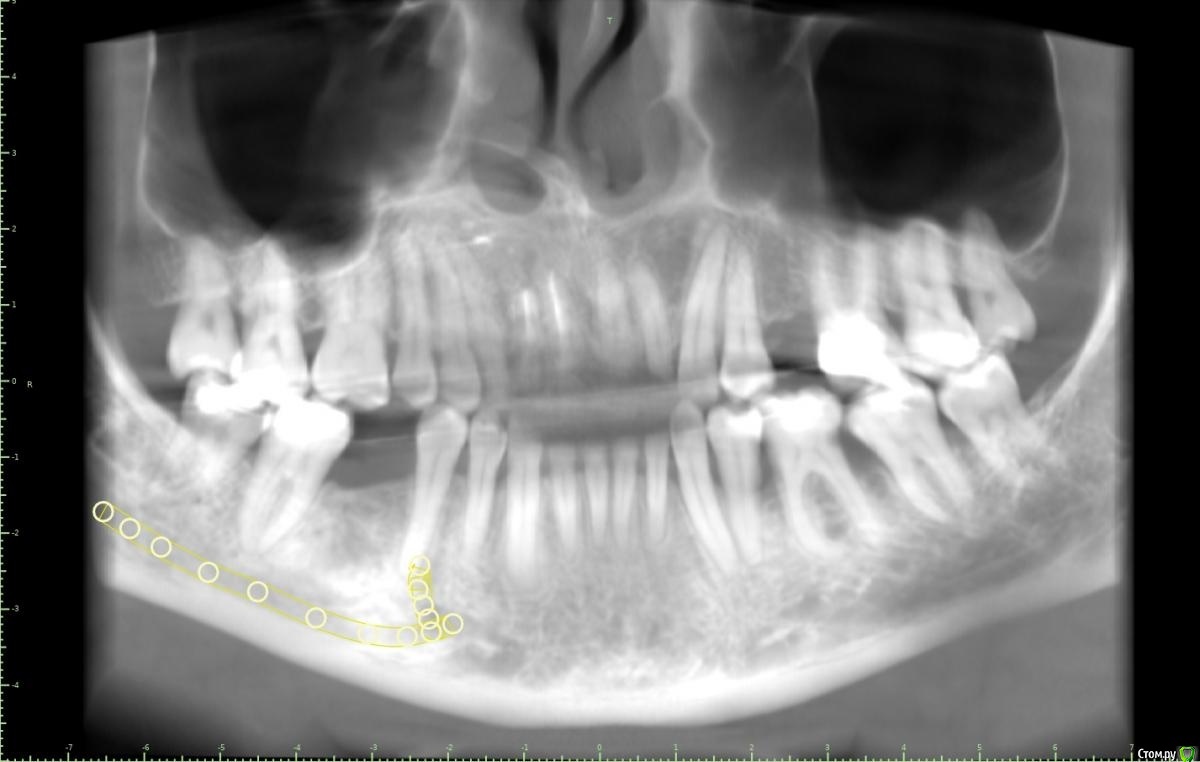

Женька Опубликовано 18 января, 2021 Поделиться Опубликовано 18 января, 2021 (изменено) Коллеги, здравствуйте!Вот такой пациент после орто. Дуги пока на месте, думаем не снимать в области отсутствующих зубов с целью удержать место до этапа протезирования.Вопрос касаемо верхнего винта.Правильно ли я понимаю, что правильным будет именно положение под цифрой 2? Хочу попробовать титановый смарт билдер, как по мне дефект как раз подходит. Или лучше мини сосиску и отсрочено в регенерат ставить. Что думаете? p.s что сверху, что снизу шестые требуют покрытия коронок, отсюда еще один вопрос, стоит ли просить ортодонта стараться ещё ангулировать 46? Просто побаиваюсь, что без этой ангуляции (если ортодонт скажет фи), не удастся сохранить зуб витальным. Ну и бонусом будет поднутрение, не получится адекватно сделать коронку и будет треугольник с едой в этой области. Изменено 18 января, 2021 пользователем Женька Ссылка на комментарий

Александр07 Опубликовано 19 января, 2021 Поделиться Опубликовано 19 января, 2021 +1 к наклону оси импланта, и сст вестибулярно можно ещё, Ссылка на комментарий